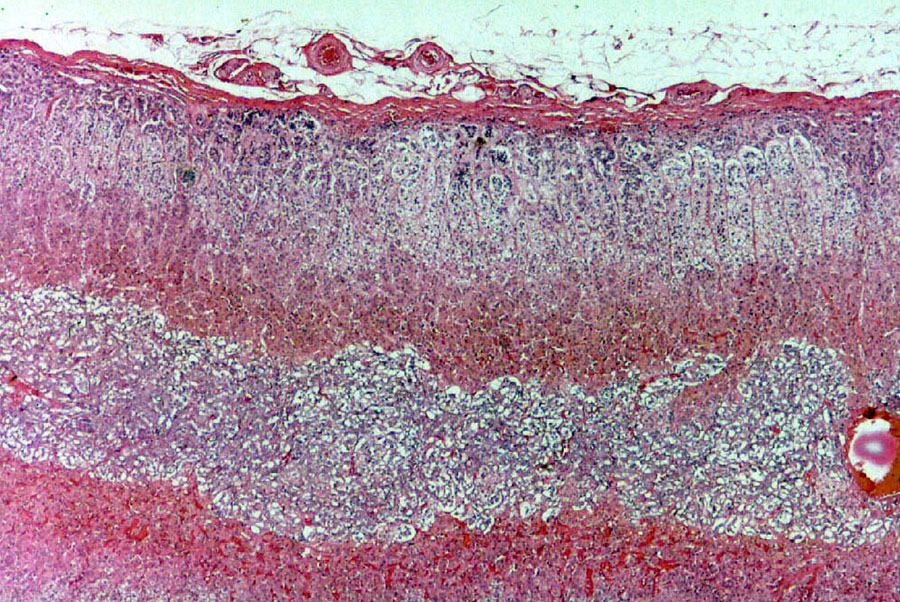

The thyroid gland can be seen on slide 691. (Slide 691 also has a section of parathyroid gland on it.).

The organization of the gland into follicles is easily seen. A very low magnification image is shown at left. The appearance of this gland in light microscope preparations is unmistakable.

The follicles are hollow balls of cells, each with a wall composed of simple cuboidal epithelium. The amorphous material present inside the follicles is colloid, an inactive storage form of the gland's secretion. Colloid incorporates the hormones thyroxin and tri-iodothyronine as part of a large (660,000 dalton) glycoprotein, thyroglobulin.

Thyroglobulin is hydrolyzed to release the active material. The capacity to store product in an inactive form is routine in exocrine organs, but it's unique to the thyroid among endocrine glands. No other endocrine gland does this. The thyroid is unique in another way: it stores its secretory product extracellularly.

In the regions between the follicles, CT cells of the septa which divide the

organ are present. As you would expect in any endocrine gland, the blood supply to the thyroid is

very good. There are capillary beds in all of the interfollicular spaces (these

can usually be identified by the presence of erythrocytes in the capillary

lumen, and/or by coagulated, stained blood plasma).

Slide 691, which is stained with Masson's stain, shows clearly the outer CT capsule of the

organ and the degree of septation. The CT fibers are

stained green, and examination under high power will reveal that wisps of CT

are present in all of the interfollicular areas, providing support for the

overall structure of the gland. You may be able to make out a few erythrocytes

in the blood vessels running through the CT.